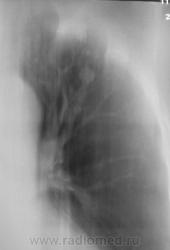

туберкулёз. Имеется небольшое расширение тени средостения в верхнем этаже.

Возможно туберкулома, но надо дифференцировать с периферическим раком лёгкого. ИМХО: средостение, вероятно не изменено, просто так вышло в положении лёжа ( стоя по обзорному снимку, тень средостения не изменена).

Валентин Львович, по-моему, это все-таки так любимые Вами "красавицы".

Периферический рак вряд ли, там же не одна тень. Без твс не обошлось.

Возраст 55 лет. Жалоб нет.

не исключить  метастазы

Пациентку забрали фтизиатры.